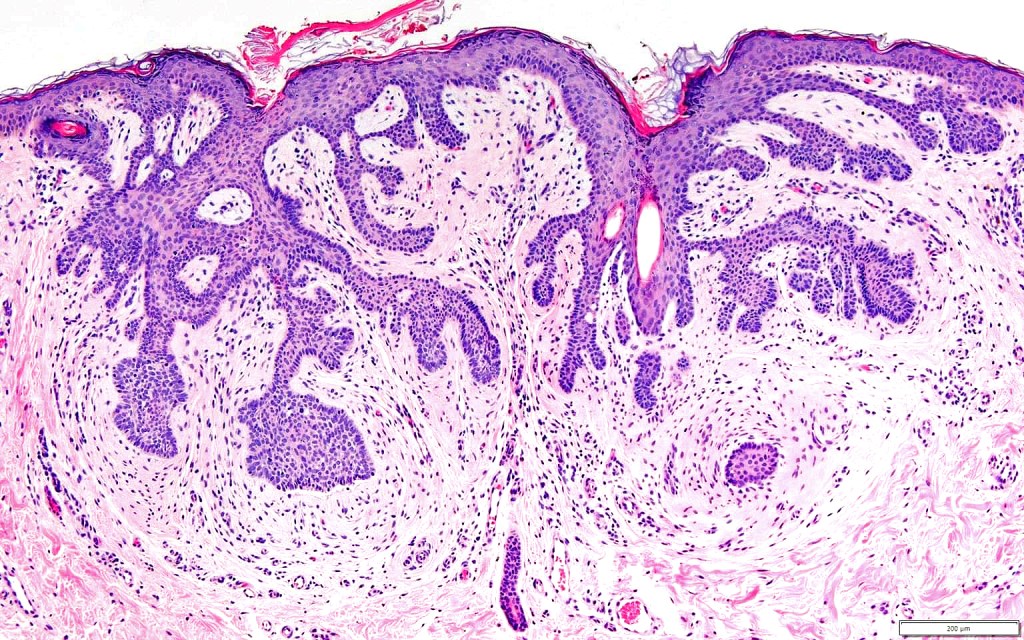

•Vertically orientated, folliculocentric, thin, anastomosing strands composed of basaloid cells embedded in a loose fibrous stroma

•+/- peripheral palisading

•Variable keratocysts

•Sometimes, in addition, trichoepithelioma-like lesions are present